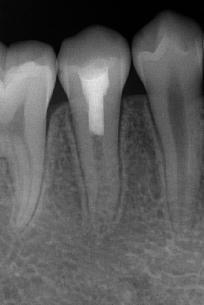

治疗前